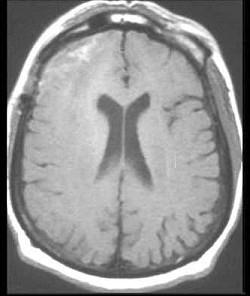

问题 男,16岁,发热、头痛半月,抽搐、意识模糊一天,CT检查如图,最可能的诊断为()

选项 A.脑水肿 B.脑积水 C.脑萎缩 D.结核性脑膜炎 E.结核性脑脓肿

答案 D